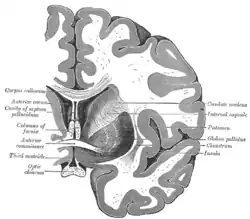

Together with the putamen, the caudate forms the dorsal striatum, which is considered a single functional structure; anatomically, it is separated by a large white matter tract, the internal capsule, so it is sometimes also referred to as two structures: the medial dorsal striatum (the caudate) and the lateral dorsal striatum (the putamen). In this vein, the two are functionally distinct not as a result of structural differences, but merely due to the topographical distribution of function.

The caudate nuclei are located near the center of the brain, sitting astride the thalamus. There is a caudate nucleus within each hemisphere of the brain. Individually, they resemble a C-shape structure with a wider "head" (caput in Latin) at the front, tapering to a "body" (corpus) and a "tail" (cauda). Sometimes a part of the caudate nucleus is referred to as the "knee" (genu).[7] The caudate head receives its blood supply from the lenticulostriate artery while the tail of the caudate receives its blood supply from the anterior choroidal artery.[8]

The head and body of the caudate nucleus form part of the floor of the anterior horn of the lateral ventricle. After the body travels briefly towards the back of the head, the tail curves back toward the anterior, forming the roof of the inferior horn of the lateral ventricle. This means that a coronal (on a plane parallel to the face) section that cuts through the tail will also cross the body and head of the caudate nucleus.